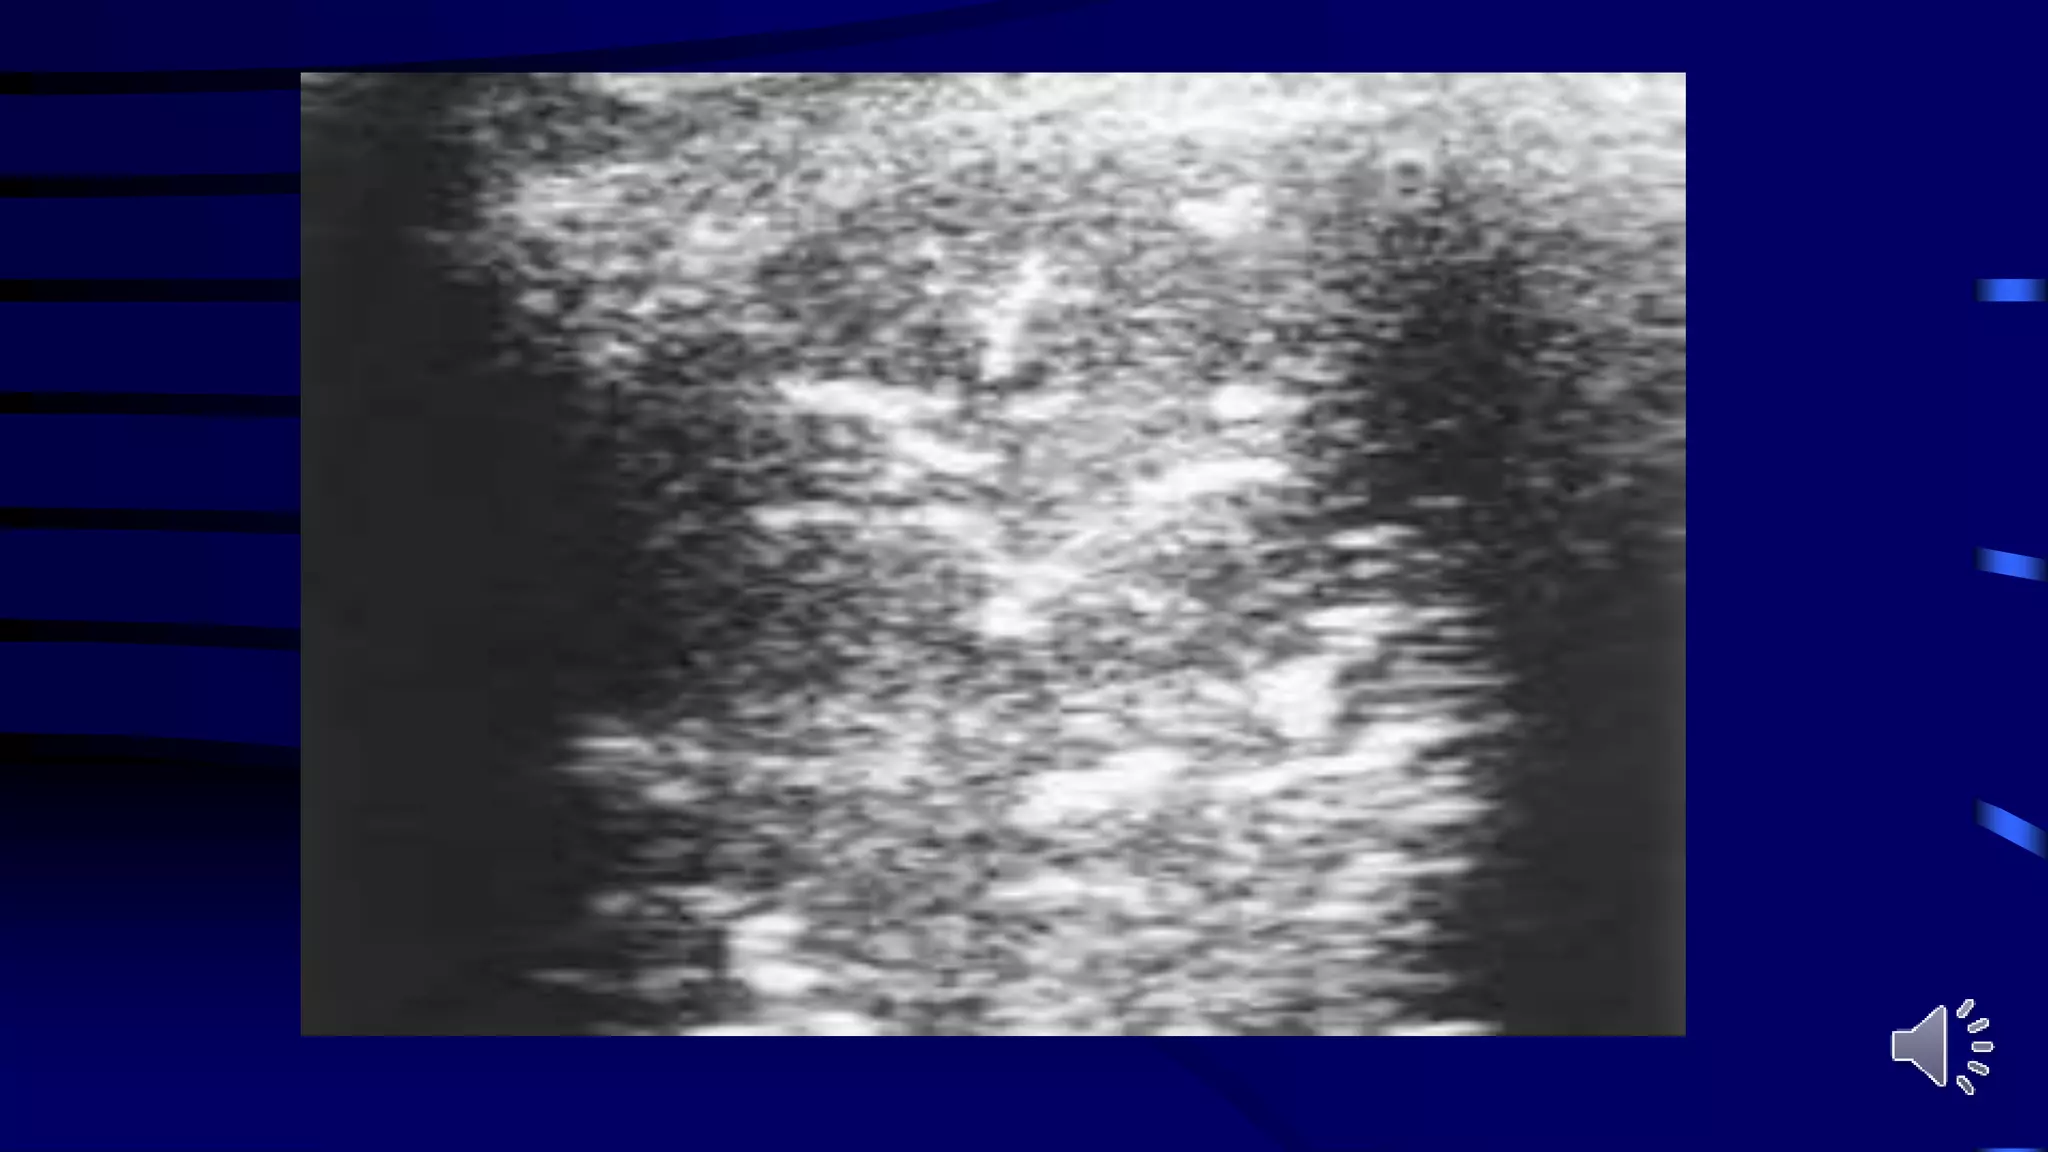

Table 5 CT and ultrasonographic features of COVID-19 pneumonia

Thickened pleura Thickened pleural line

Ground glass shadow and effusion B lines (multifocal, discrete, or confluent)

Pulmonary infiltrating shadow Confluent B lines

Subpleural consolidation Small (centomeric) consolidations)

Translobar consolidation Both non-translobar and translobar consolidation

No Pleural effusion No Pleural effusion

More than two lobes affected Multilobar distribution of abnormalities

Focal B lines is the main feature in the early stage and in

mild infection; alveolar interstitial syndrome is the main

feature in the progressive stage and in critically ill

patients; A lines can be found in the convalescence;

pleural line thickening with uneven B lines can be seen in

patients with pulmonary fibrosis